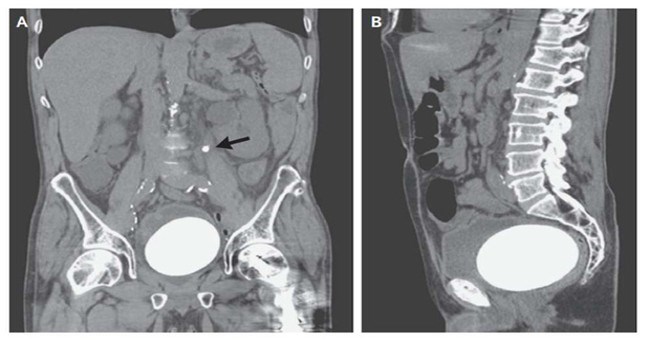

• Đau bụng, người đàn ông nhập viện chụp X-quang và thu được một kết quả đáng sợ

Đau bụng, người đàn ông nhập viện chụp X-quang và thu được một kết quả đáng sợ